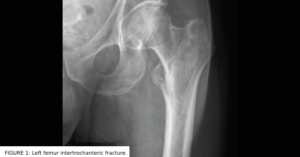

femur problem solvers feb 2024